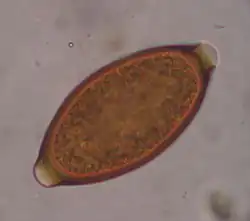

Egg of T. vulpis

Trichuris vulpis is a whipworm that lives in the large intestine of canines in its adult stages. Out of different types of worms, Trichuris vulpis is one of the smaller worms with a size ranging from 30–50 mm in length. As the name suggests, the worm has a whip-like shape with distinct features including a small, narrow anterior head, which is the digestive part of the worm, and a larger posterior tail, which is the reproductive part of the worm. Eggs from T. vulpis are oval shaped with bipolar plugs and contain a thick outer shell. Their sizes range from 72–90 μm in length and 32–40 μm in width.[1] Because of their thick outer shell, T. vulpis eggs are very resistant to environmental extremes such as freezing or hot temperatures, thus allowing for their long viability in the outside world.[2]

Infection of this parasite can be confirmed with detection of eggs in the canine's feces. Adult T. vulpis females can produce more than 2,000 eggs per day. These eggs can be detected in the canine's feces by the fecal flotation method.[14] This method utilizes the differences of specific gravity of eggs, fecal debris, and the flotation solution.[15] Although these eggs are dense, the use of proper fecal flotation technique using a sugar solution and centrifugation can increase the chances of identifying these eggs in a fecal sample.[16] Multiple fecal samples may need to be tested as the eggs may be shed periodically.[17]